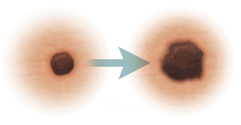

Evolving

Changes in the way the mole looks over time